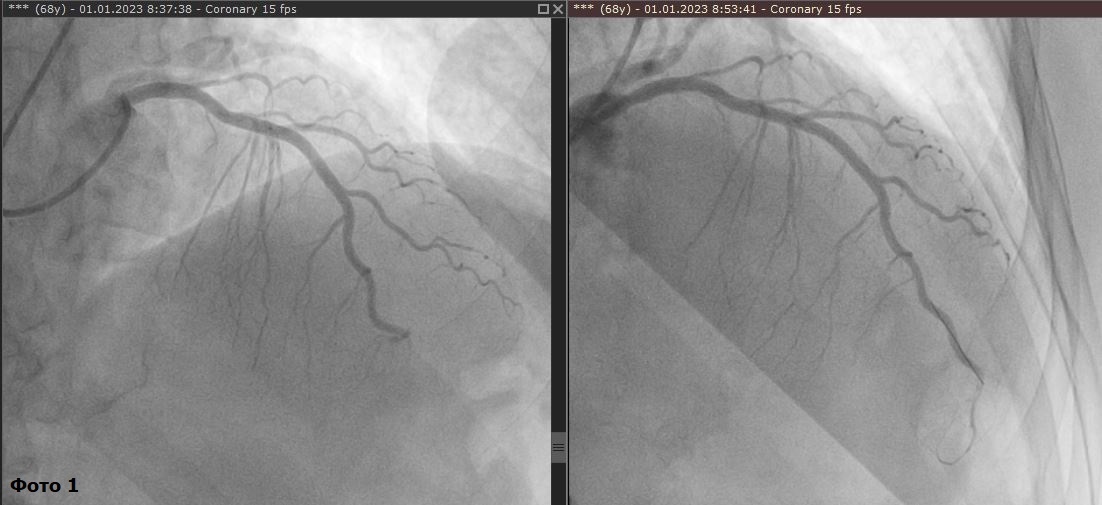

Пациент 68 лет. Поступил с диагнозом острый инфаркт миокарда 1 января 2023 года. Выяснилось, что в артерии сердца образовался или застрял тромб, в достаточно нетипичном месте. Артерия сердца была вылечена с помощью имплантации внутрисосудистого протеза (коронарного стента).

Фото 1: до лечения (окклюзия, закупорка дистальной, нижней трети крупного сосуда); после лечения (установлен стент, артерия запущена).